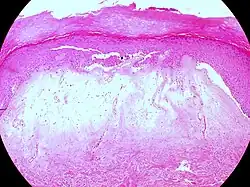

Typische histopathologische Merkmale des Lichen sclerosus sind eine Atrophie der Epidermis mit vakuolärer Degeneration der Keratinozyten (hornbildende Zellen der Epidermis) in der basalen Zellschicht und Sklerose der korrespondierenden Dermis. Der Sklerosezone grenzt zur Tiefe ein zumeist bandartig angeordnetes Entzündungsinfiltrat aus Lymphozyten an. Weitere mögliche Veränderungen sind eine unregelmäßige Akanthose (Verbreiterung des Stratum spinosum der Epidermis) und Hyperkeratose der Epidermis (hypertrophische Form), auf behaarter Haut mit Hyperkeratosen der Haarfollikel.[19]

In extragenitalen Läsionen fehlt häufig die Atrophie und das Entzündungsinfiltrat kann eosinophile Granulozyten enthalten. In der Dermis zeigen sich hier häufiger aufgeweitete kleine Blutgefäße.[20][21] Klinisch bullöse Läsionen gehen mit einem dermalen Ödem bis hin zur subepidermalen Blasenbildung einher.

Lichen sclerosus (hypertrophische Form) -